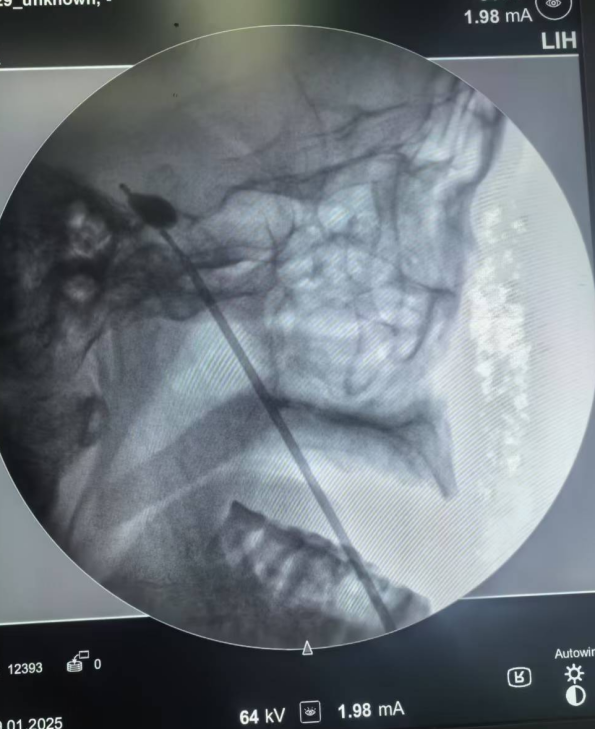

该微创手术通过影像引导,精准定位三叉神经半月节,置入球囊短暂压迫即可阻断痛觉信号异常传导。手术过程时间短、定位准确,患者术后即刻感受疼痛消失,2-3天即可出院。相较于传统手术,具有创伤小、风险低、恢复快、费用亲民等显著优势,尤其适合高龄、基础疾病多的患者。